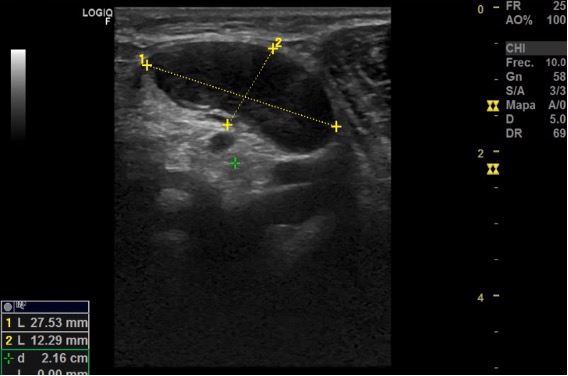

Ecografía: Conglomerado adenopático en axila izquierda. Adenopatía más grande (30 x 40 mm) hipoecogénica, redonda con pérdida del hilio graso, de aspecto infiltrativo y con captación Doppler. Adenopatías infraclaviculares de 27,5 x 12,2 y una glomerulación de 13,9 x 17,1 mm hipoecogénicas con pérdida de estructura normal. Adenopatías perihiliares hepáticas de 9 x 23 mm y otro 26 x 17; perihiliar esplénica de 12 x 4 x 5 mm, e inguinal izquierda de 9,3 x 7,8 mm.